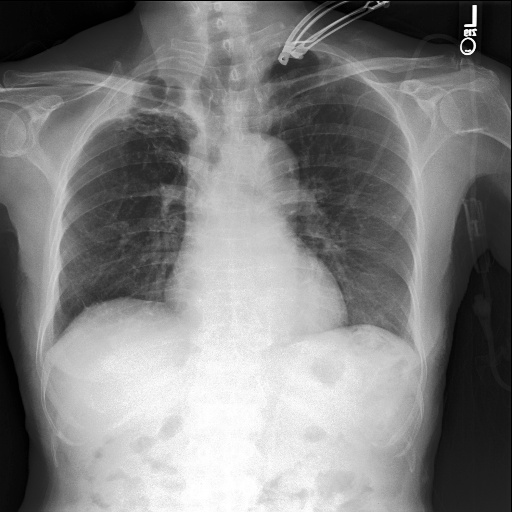

To assess whether dataset-specific signals are present in images independent of pathology, we train a 4-way classifier to predict dataset source (MIMIC-CXR, CheXpert, ChestX-ray14, PadChest). We use DenseNet-161, which achieved the highest internal AUROC and AUPRC in three of the four datasets in our domain shift analysis. Using the strongest-performing architecture ensures that any ability to distinguish dataset sources reflects genuine learnable signatures rather than limitations of model capacity. This DenseNet-161 backbone is trained from scratch on our four training datasets, using only pixel data. Performance is evaluated using Sensitivity, Specificity and F1-Score for each of the four classes (source datasets). As chance-level accuracy is 25%, substantially higher performance would indicate that non-pathological features (e.g., text markers, intensity scaling, acquisition artefacts) allow models to distinguish datasets. Results are shown in Table 5. Example images from each source dataset are shown in Figure 5.

The DenseNet-161 dataset-source classifier achieved near-perfect performance across all four classes (source datasets), far exceeding the 25% chance level. This indicates that public chest radiography datasets contain strong, easily learnable site-specific signatures. which are deeply embedded in the data. These signals are unrelated to pathology and instead likely reflect differences in acquisition protocols, scanner hardware, image post-processing pipelines, or embedded text markers. This finding highlights a critical shortcoming of current public benchmarks - models may exploit non-clinical cues that distinguish datasets rather than learning generalisable representations of disease.

Refer to caption

(a) CheXpert

(b) MIMIC-CXR

(c) ChestX-ray14

(d) PadChest

(e) CheXpert

(f) MIMIC-CXR

(g) ChestX-ray14

(h) PadChest

Figure 5: Example chest radiographs from MIMIC-CXR, CheXpert, ChestX-ray14 and PadChest. Each image contains text artefacts.